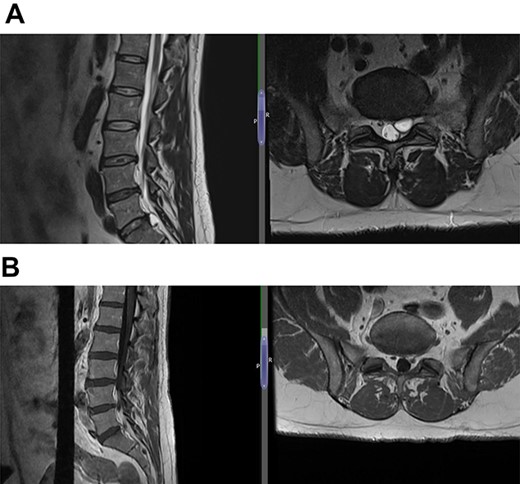

(A) Case 4—an initial MRI showing multilevel degenerative disc disease and a cyst at the lumbar L5/S1 which is causing impingement on the left S1 nerve root, and (B) case 4—comparison was made with the previous MRI; post-contrast scan shows that the L5-S1 left-sided cystic features have nearly diminished; no neoplastic lesion is detectable.